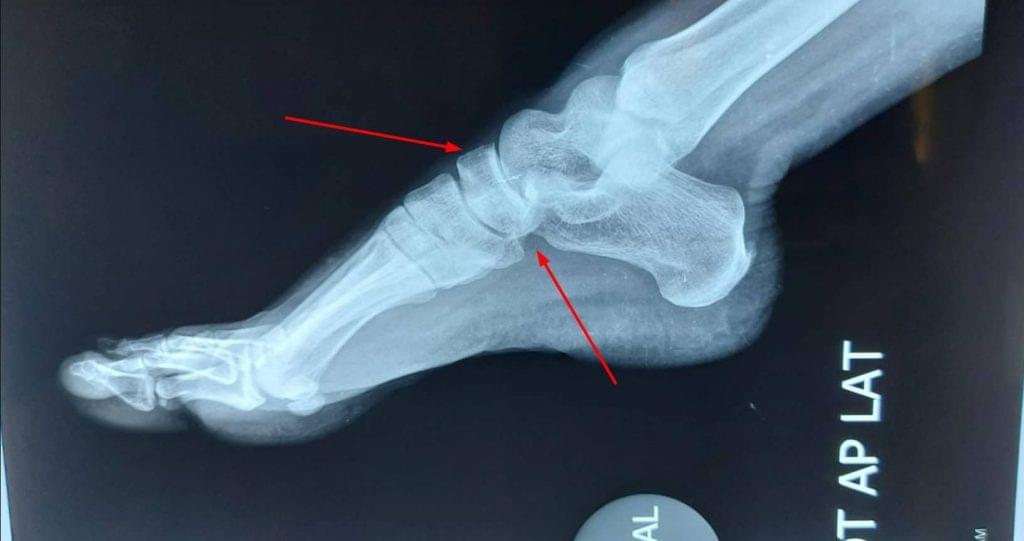

Talonavicular joint pain treatment: Talonavicular joint is part of a 3 joint complex in the foot which all work together for smooth mobilization of the foot and walking. Damage to one joint or bone can affect other joints and disturb walking and create chronic pain and swelling.

Diseases of the Talonavicular joint can be due to injury such as fall, accident, twisting of the foot which cause fracture of the navicular bone and if not treated in time, lead to chronic pain and arthritis.

Another common problem is wear and tear in the bones leading to Arthritis of the Talonavicular joint. Other rare conditions such as avascular necrosis of Talus or Navicular bone, stress fracture, tumor, and unknown infections can also affect this joint complex.